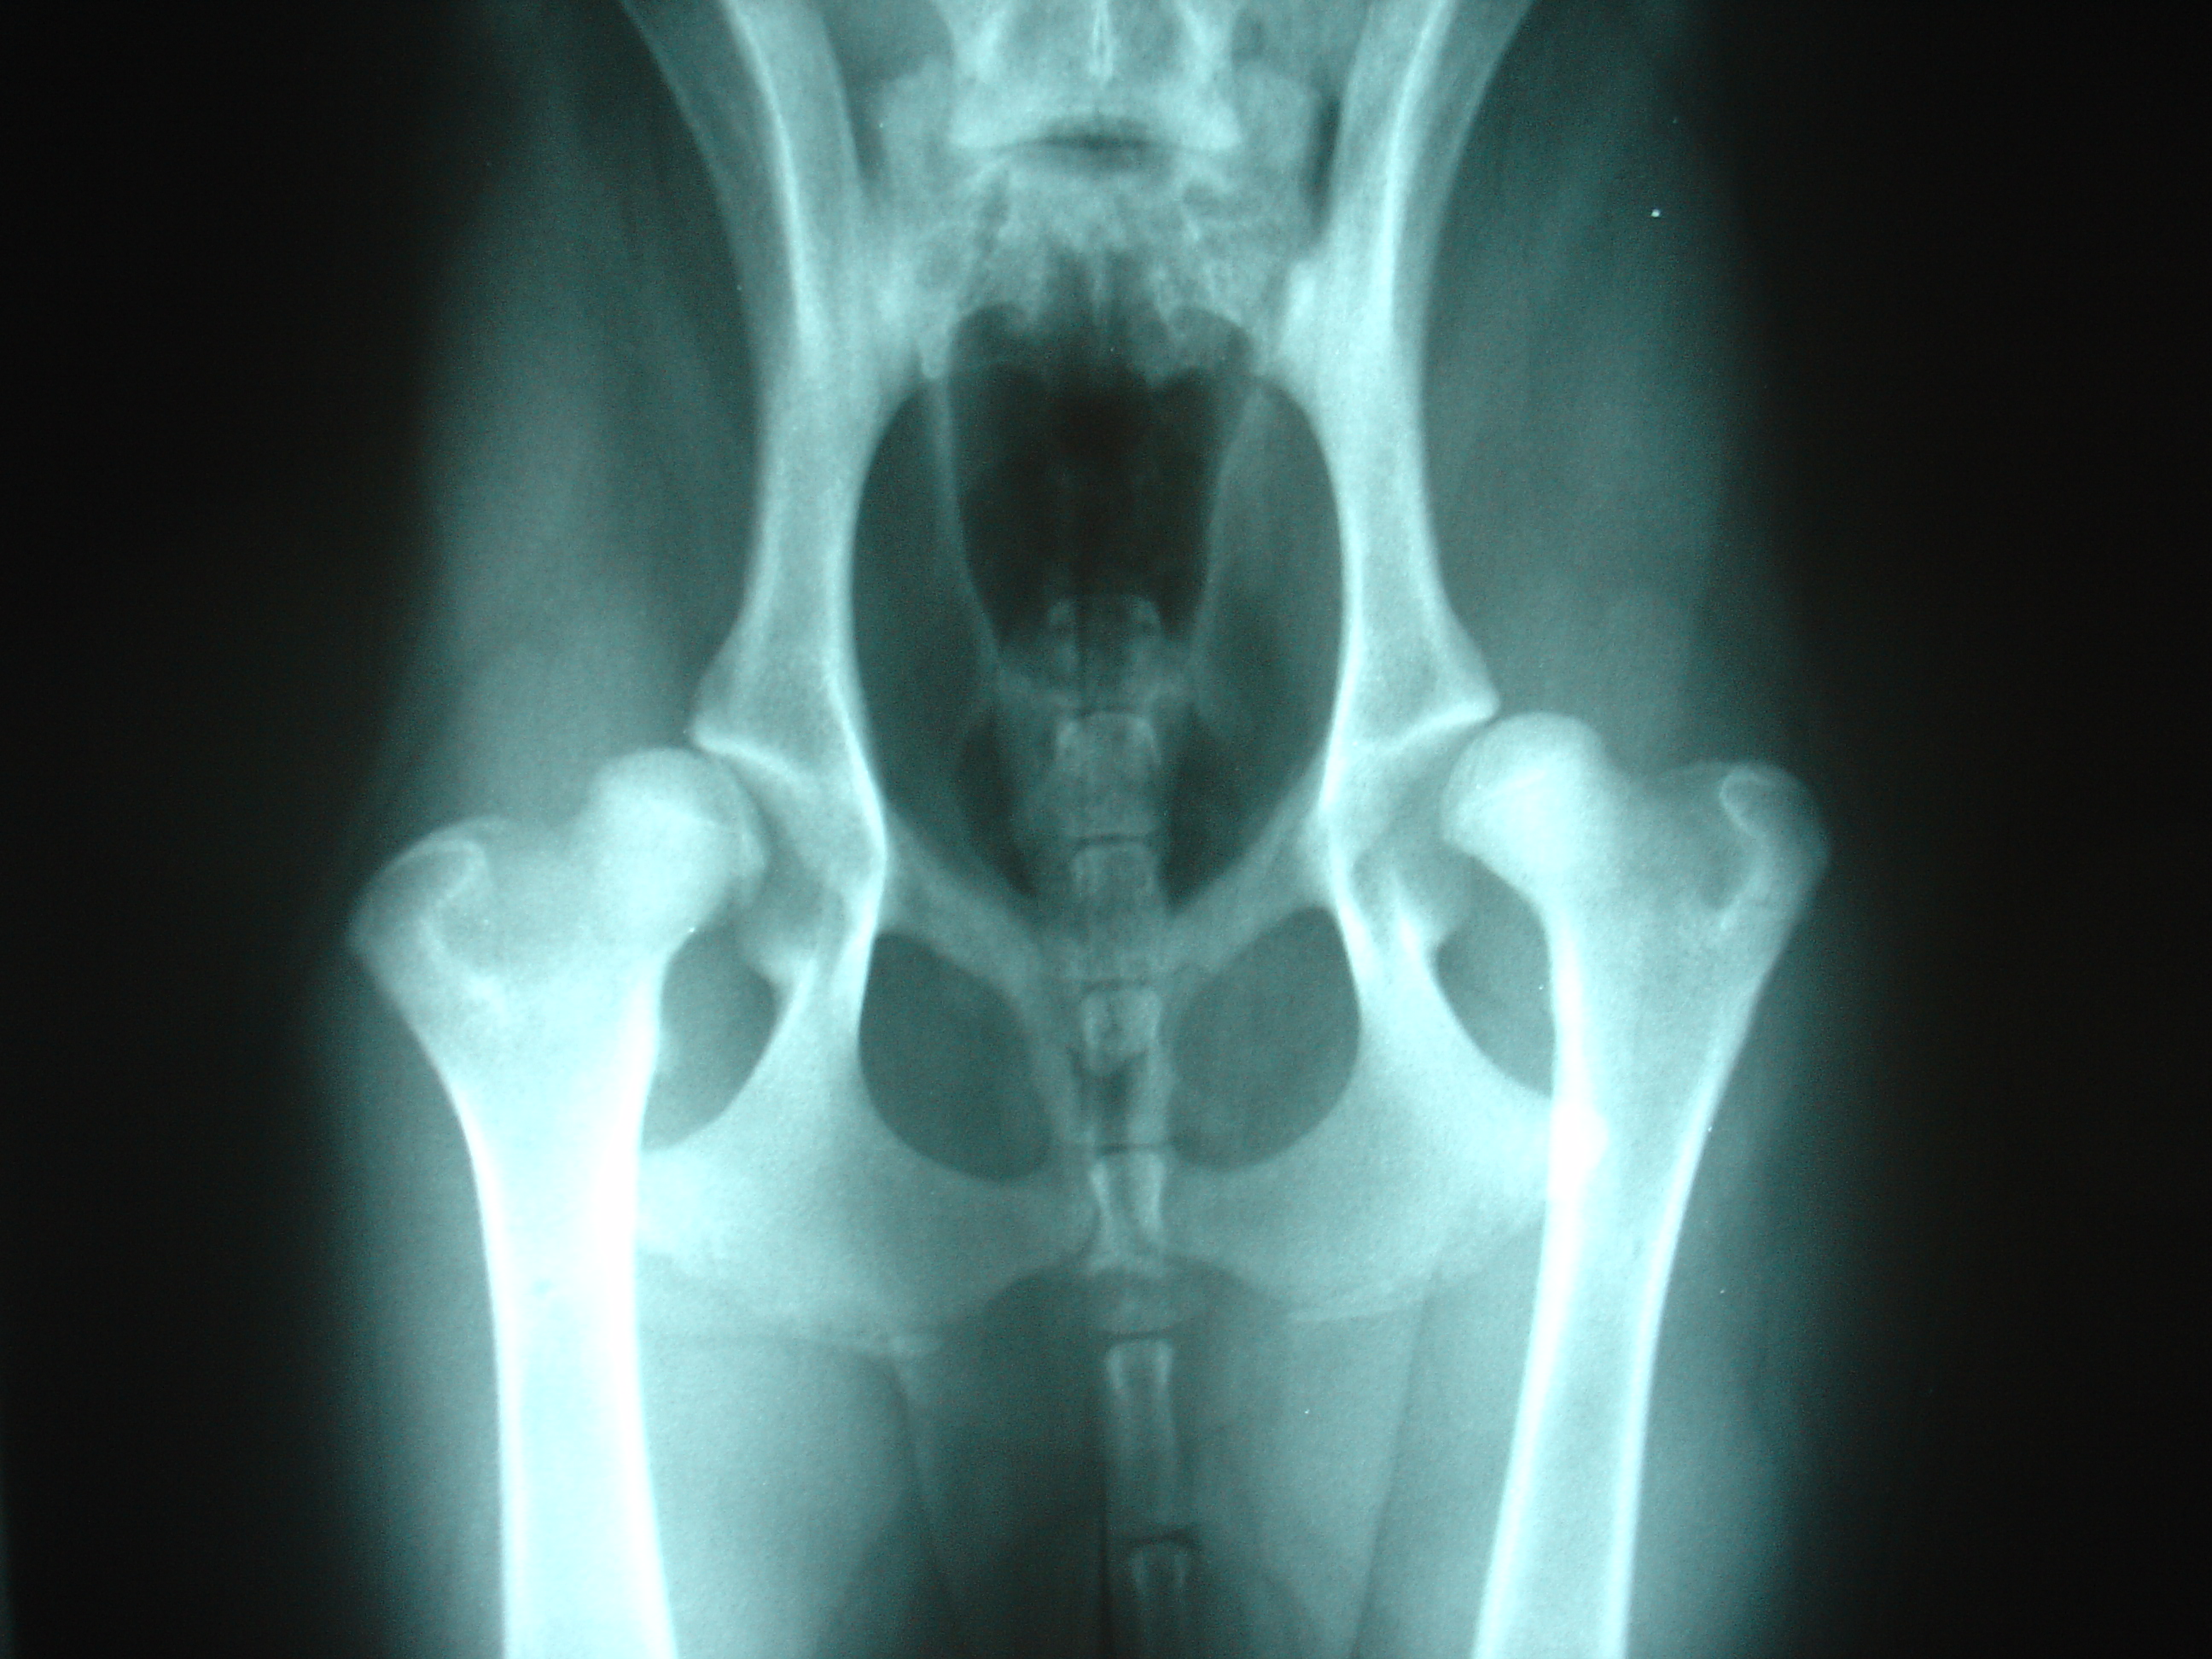

Reto Veterinario: Diagnostiquemos a esta gatita con sed

Respuesta correcta «e» Nuestra paciente debe ser reevaluada. Entre las patologías posibles, la infección urinaria es la que debemos tener en cuenta siempre en diabéticos.…